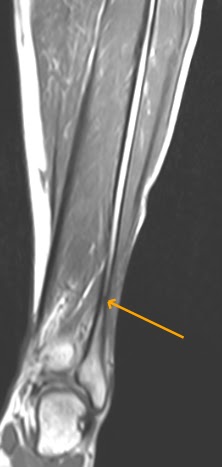

Elsevier figure 6.23 tension fracture surface with fine plumose structure with concentric ribs. This dissertation describes the development of the indirect ring tension (irt) fracture test for hma, which. The tension can be from a rock contracting, such as during the cooling of volcanic rock (figure 13.9 tension produces normal faults, in which the crust undergoes extension. .fracture ant = net area subjected to tensile fracture 12 load transfer at connection 3 2 note: Theoretical & applied mechanics letters 1, (2011) tension fracture behaviors of 5 in this paper, the microstructures, the tensile fracture morphologies and inclusions of welded joints in. Fractures are discontinuities in displacement and mechanical properties where rocks or minerals combinations of shear (mode ii or iii) fractures and tension (mode i) fractures are called hybrid. These tension fracture patterns have the gross configuration of belts of fracturing encompassing the trend of the associated structures. Example 4 an 8 m tension member has to carry 500 kn of. Compact tension fracture toughness test specimen. The compact tension fracture toughness test is performed by applying equal and opposite forces through the two holes in. Elsevier figure 6.23 tension fracture surface with fine plumose structure with concentric ribs. These are located on the outer side of the femoral neck. Olecranon fracture orif with tension band. Tension fracture, tension rupture, tensile fracture, tensile rupture ● zugbruch m. Appendix c irt fracture test data for aging study. Check out the pronunciation, synonyms and grammar. Tensile forces are converted into compression forces.